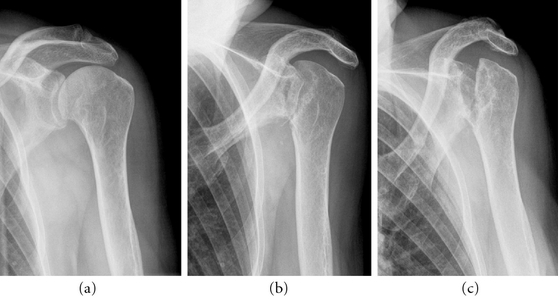

2-Year-Old Has Rare ‘Vanishing Bone’ Disease

An Ottawa County boy is battling a disease so rare, less than 300 cases have been reported in the entire world. Two-year-old Leo Aguillon went to the doctor for pneumonia a couple weeks ago, but a chest x-ray and CT scan showed the unimaginable: half of the bones in his chest were gone. “They found […]